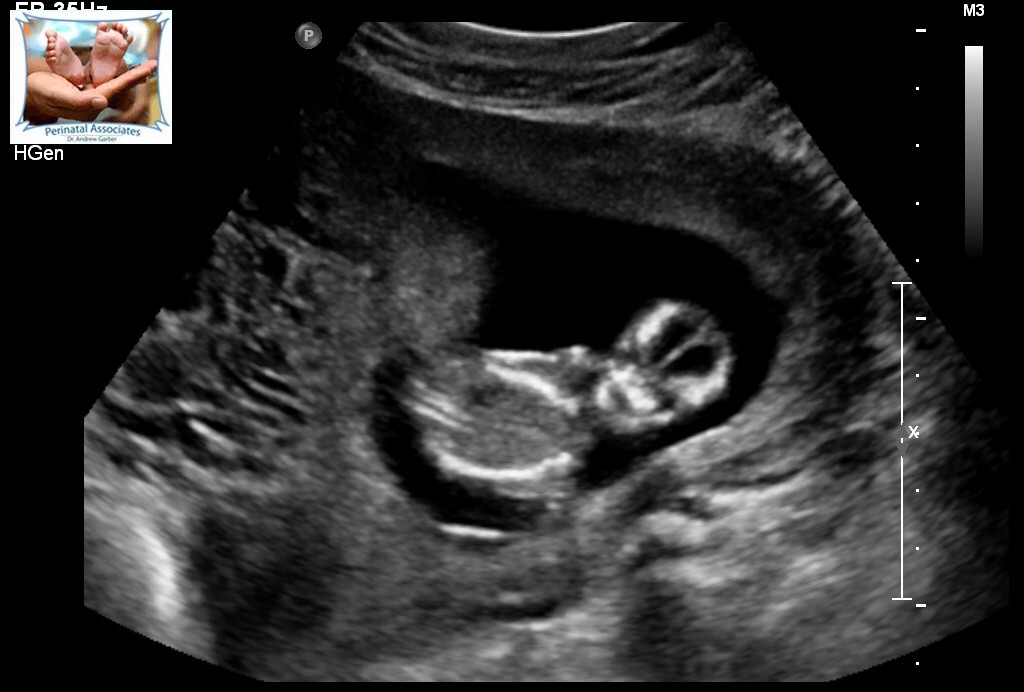

This is from 13 weeks. Can anyone guess what gender? The tech could not find a penis or nub like thing (looked for 30 minutes) and determined she is not convinced about it being a boy but could not exactly see the girl parts.Attachment 26141Attachment 26142Attachment 26143Attachment 26144